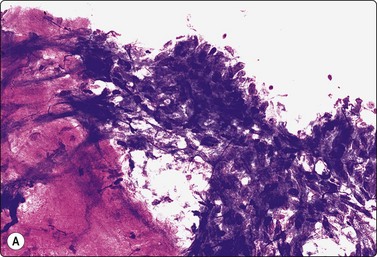

Fig. 4.4 Amyloid tumor

Clumps of amorphous acellular purple material (MGG, HP).

Apple-green birefringence with Congo red stain.

Solitary deposits of amyloid, so-called amyloid tumors, are occasionally found submucosally in the hypopharynx, the larynx and other parts of the upper respiratory tract. Amyloid stains an intense magenta color with MGG, less specific yellowish-green with Papanicolaou. It has a fairly dense amorphous texture with a finely fibrillar rather than hyaline structure discernible in high power. In FNB smears, the amyloid may be associated with histiocytic giant cells, lymphocytes or epithelial and/or mesenchymal cells from surrounding tissues (see also Chapter 14).

Problems and differential diagnosis

The appearances of amyloid in cytological smears are not always characteristic enough to be diagnostic. It can be confused with dense thyroid colloid or hyalinised fibrous stroma.39 Its nature should therefore be confirmed by staining with Congo red and polarisation. In the head and neck, the possibility of origin from medullary thyroid carcinoma, primary or metastatic, must always be considered, and immunostaining for calcitonin performed.